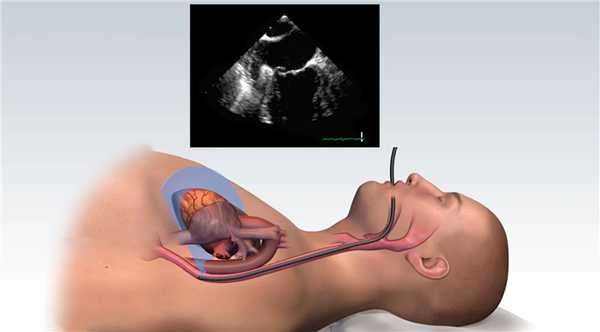

Чреспищеводная эхокардиография (ЧПЭхоКГ) - это разновидность УЗИ сердца с применением специального датчика, который вводится в пищевод пациента. Пищевод расположен в непосредственной близости к сердцу и коронарным сосудам, благодаря этому на пути следования ультразвуковой волны нет акустических препятствий в виде костей, мышц и клетчатки. Следовательно, диагностические возможности чреспищеводной эхокардиографии существенно шире, чем у обычной ЭХО-КГ.

Чреспищеводная эхокардиография (ЧПЭхоКГ) - метод ультразвуковой диагностики сердца с использованием специального датчика, вводимого через пищевод.

Для уменьшения рвотного рефлекса производят поверхностную анестезию глотки. После в пищевод вводится датчик, расположенный на гибком зонде (методика схожа с гастроскопией). Во время исследования пациент находится в положении на левом боку лицом к врачу, проводящему исследование. Правое колено пациента согнуто и располагается спереди от левой ноги, голова слегка наклонена вперед. Для защиты датчика от перекуса используют загубник. Датчик перед введением обрабатывают ультразвуковым гелем. Введение датчика в пищевод проводится врачом. Датчик располагается в средней части пищевода на уровне сердца. Отсутствие преград для ультразвука и малое расстояние до структур сердца позволяет в разы повысить разрешающую способность исследования и получить информацию, недоступную при трансторакальном исследовании. Исследование длится 5 - 15 минут, что зависит от объема требуемой информации.

Во время процедуры датчик, испускающий ультразвук, располагается в пищеводе. Это гораздо ближе к структурам сердца, которые труднодоступны для оценки при обычной эхокардиографии с чрескожным датчиком. Только чреспищеводная ЭХО-КГ позволяет увидеть тромбы в ушках левого предсердия. При ее помощи можно получить гораздо больше информации об опухолях сердца и образованиях на клапанах, чем при стандартном УЗИ (ДЭХО-КГ). Исследование точнее определяет плотность прикрепления тромбов, что позволяет определить крайне важный прогностический показатель - риск их отрыва.

Чреспищеводная эхокардиография (ЧЭ или ЧпЭхоКГ) позволяет с помощью высокочастотных звуковых волн (ультразвука) получить подробные изображения вашего сердца. Эхопреобразователь, излучающий звуковые волны, прикреплен к тонкой трубке (толщина варьируется от 9 до 11 мм), которая проходит через рот, спускается по горлу и в пищевод. Поскольку пищевод находится близко к верхним камерам сердца, можно получить очень четкие изображения этих структур и клапанов сердца.